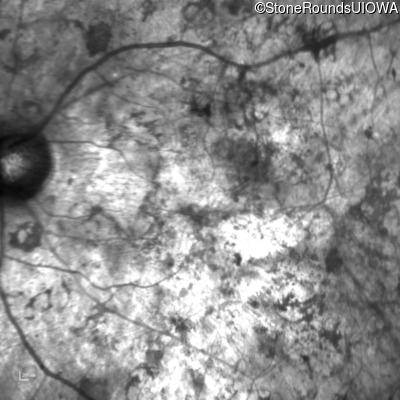

Age at visit: 33 years

OD OS